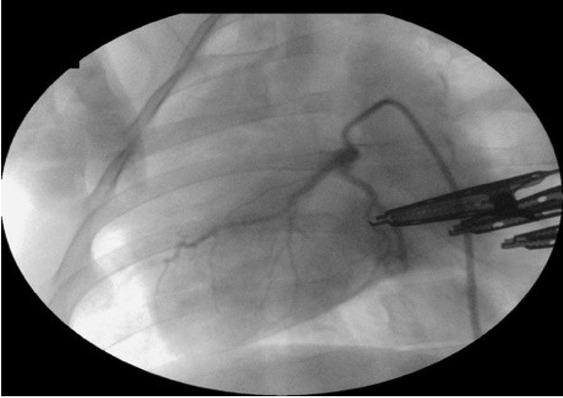

Then a 0.014ʺ balance middleweight 300 cm angioplasty guidewire (Abbott, Santa Clara, CA, USA) was inserted through the catheter and placed under fluoroscopic control (Symbol; General Medical Merate SpA, Seriate, Italy) in the proximal segment of the LAD. A 3.0 × 10 mm over-the-wire angioplasty balloon (Sprinter; Medtronic) was placed on the guidewire. The balloon was inflated to 6 atm and held at that pressure for 30 min for complete LAD occlusion. Arterial closure was confirmed by angiography (Fig. 2), while MI was diagnosed by ST-segment elevation on the 12-lead ECG (Fig. 3). Additionally, MI was confirmed by histopathological analysis of myocardial tissues collected from the animals when euthanised 4 weeks after the procedure.

Fig. 2

Coronary angiography presented occlusion of the proximal segment of the left anterior descending artery achieved with an angioplasty balloon in a female pig subjected to myocardial infarction in a modified anaesthetic protocol